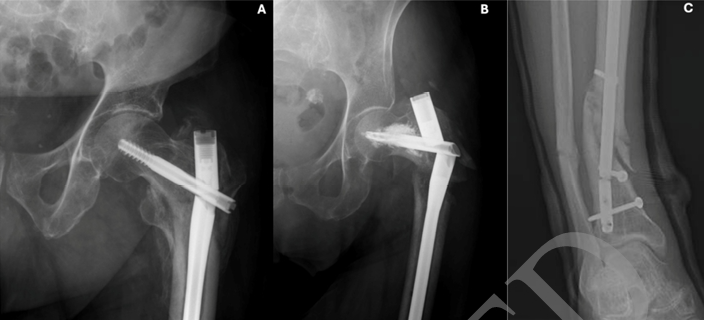

骨不连对患者生活质量的影响极大,甚至超过充血性心力衰竭、2型糖尿病和心肌梗死等慢性疾病。临床上,当内植物因疲劳断裂时,骨不连的诊断往往得以明确(图1)。

手术案例2:一例87岁男性患者长头髓股骨髓内钉的取出过程(图1A)